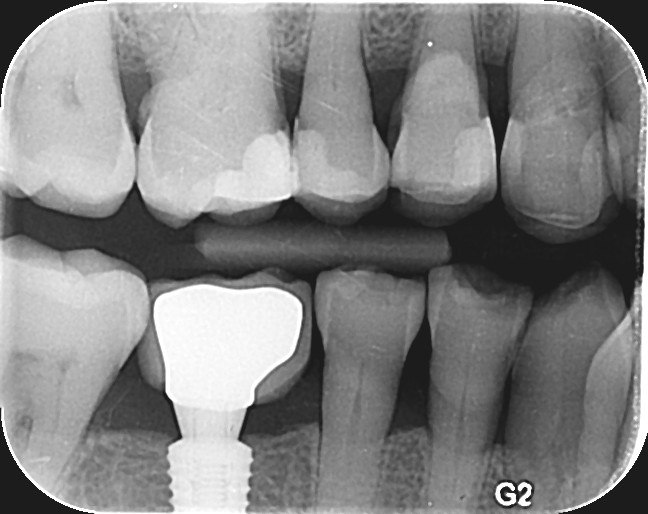

1. Which surfaces shows dental caries?

2. Which surface needs restoration?

4. Which surface needs restoration?

5. Which surface needs restoration?

8. Which surface needs restoration?

14. Which surfaces shows recurrent caries?

15. Which surface shows recurrent caries?

18. Which surfaces need restoration?

25. What are the caries level in distal surface of the tooth # 1.4, Mesial surface of the tooth # 1.5 respectively?

32. Which surfaces needs restoration?

33. What is the caries level of the distal surface of the tooth # 1.6?

34. What is the proper tretment for mesial surface of the tooth # 1.6?

38. Which surfaces shows recurrent caries?

40. Which surfaces shows recurrent caries?

42. Which surfaces shows recurrent caries?

43. Which surface shows recurrent caries?

44. What is the caries level of mesial of the toth # 1.6?

45. Which surface shows recurrent caries?

46. Which teeth shows recurrent caries?

47. Which surface(s) shows recurrent caries?

50. Which surface(s) shows recurrent caries?